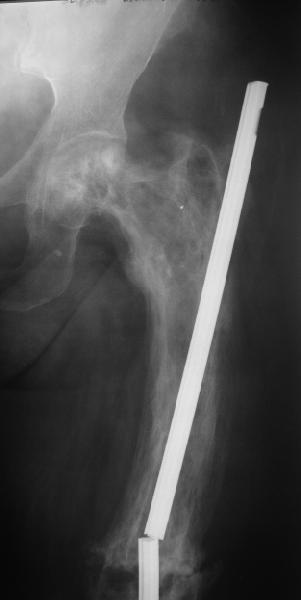

Еще один пример. Пациентка с юга России, прислала рентгенограммы через год. На сегодня прошло 2 г. 8 мес. после операции. Несмотря на не очень убедительный процесс сращения, пациентка ходит. Учитывая остеопороз при Педжете, решили, что динамизировать вообще не нужно.